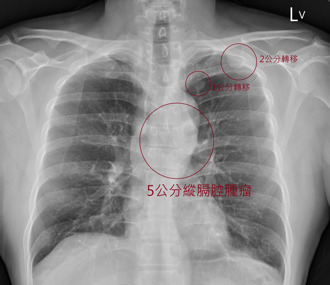

• 没有不舒服!40岁男不菸不酒 X光一照「已癌末到处转移」

没有不舒服!40岁男不菸不酒 X光一照「已癌末到处转移」

胸腔科医师苏一峰今天分享,一名40多岁男性,平时不抽菸、不喝酒,生活作正常,身体也没有任何不适,却在健康检查时发现胸部X光有一颗5公分大的肿瘤,且已是癌症末期,癌细胞已转移到多处,让苏一峰感慨「人完全没有不舒服,结果是癌症末期。」